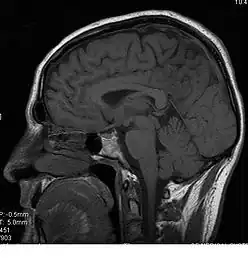

Le corps calleux (ou corpus callosum) est une commissure (moyen d'union entre deux parties) transversale du cerveau présente chez les mammifères placentaires[1]. C’est un faisceau d'axones (fibre nerveuse qui correspond au prolongement long, mince et cylindrique du corps cellulaire d'un neurone) interconnectant les deux hémisphères cérébraux. C'est la plus importante commissure du cerveau, car elle relie les huit lobes du cerveau entre eux (lobes frontaux, temporaux, pariétaux et occipitaux gauche et droit). Le corps calleux assure donc le transfert d'informations entre les deux hémisphères et ainsi leur coordination. Les autres commissures sont le fornix, le cingulum et la commissure blanche antérieure.

D’avant en arrière, on peut délimiter trois structures :

- le « genou » et le tiers antérieur du corps calleux (bec ou rostrum) sont ainsi formés par les fibres qui unissent les deux cortex (lobes) frontaux ;

- le tiers moyen (ou tronc) est formé par les fibres qui unissent les cortex pariétaux et temporaux ;

- la partie la plus postérieure, (bourrelet ou splenium), est formé par les fibres qui unissent les deux cortex occipitaux.